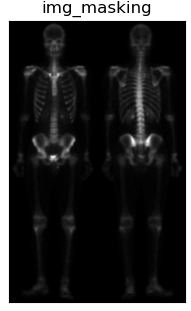

| 将滤波后的图sobel与图img_laplacian进行相乘,保留变化强烈的细节,平滑噪声 |

| 将相乘得到的图masking叠加到原图上 |

| 最终将各结果进行对比显示 |